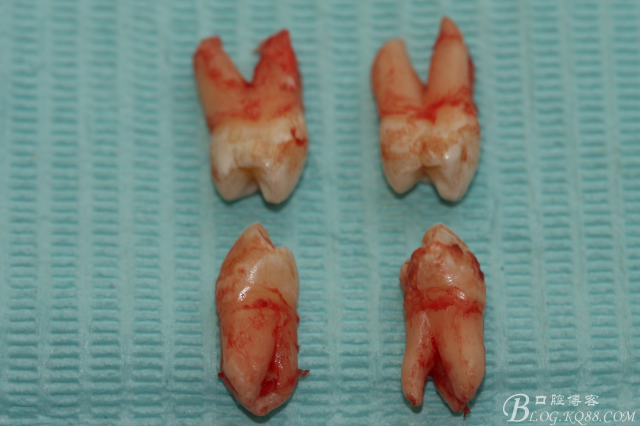

患者:江某某、男、14歲。因正畸治療需要拔除上下頜四顆第一前磨牙。按醫(yī)囑,局麻下拔除四顆第一前磨牙。牙齒拔除后發(fā)現(xiàn)四顆牙齒均為三個(gè)根,頰側(cè)兩根,腭側(cè)一個(gè)根。上頜第一前磨牙偶見三根。下頜第一前磨牙左右兩側(cè)均為三根,實(shí)屬罕見。發(fā)圖片,與同仁共勉。

手術(shù)圖片:

5.上頜離體第一前磨牙牙根形態(tài)

6.下頜離體第一前磨牙牙根形態(tài)

7.四顆離體上下頜第一前磨牙牙根形態(tài)